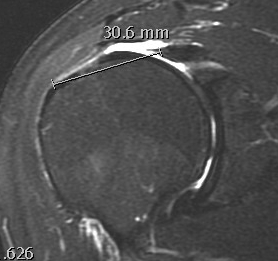

MRI

Measure tear in the coronal and sagittal plane

Massive rotator cuff tear of the supraspinatus and infraspinatus tendon - retracted to glenoid

MRI predictors of reparability

- 60 patients with large and massive tears

- irreparability associated with retraction to or beyond glenoid

- irreparability associated with tangent sign / advanced fatty infiltration / superior migration humeral head

- 120 patients with large and massive tears

- irreparability associated with modified grade III Patte (retraction to medial 5th humeral head)

- associated with 94% chance or irreparability

- irreparability also associated with reduce acromiohumeral distal / superior migration humeral head

Examples of rotator cuff tears that are likeley irreparable